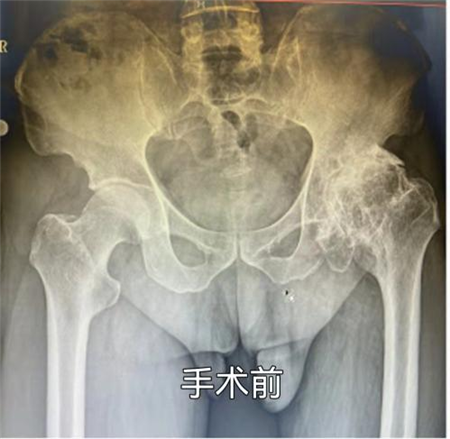

我院骨外二科的医师给王先生做了系统的髋关节检查,发现正常人的髋关节本该是杵臼关节,在各个方向都应该有一定的活动度,而王先生的左髋关节基本不能活动了,而且左腿要比右腿短缩3厘米。经X线检查,发现王先生的左髋臼窝磨损变形非常严重,股骨头也坏死了,髋关节长满了骨赘,包裹在了曾经骨折的部位、坏死了的股骨头及磨损变形的髋臼窝周围,这在医学上被称为股骨头坏死、髋关节骨关节炎。目前治疗这种疾病的有效方法只有全髋关节置换。通常髋臼磨损越重,骨赘越多,患肢短缩越多,手术难度就越大,王先生此时的病情需尽快进行手术。医生们根据患者病情积极制定手术方案,还给王先生做了思想工作,最终他接受了门诊医师全髋关节置换的建议。经过术前的周密准备,于2021年12月23日,在我院骨外二科医护人员的努力下,使用几乎永不磨损的陶瓷-陶瓷界面全髋关节假体,成功为王先生实施了人工全髋关节置换术。因为受伤时间太久未进行系统治疗,手术中清理出了大量的增生骨赘,髋臼缺损部位采用残存的股骨头重建了髋臼形态。手术后,王先生表示,左髋关节不痛了,睡觉踏实了,可以长距离地走路,走路姿势也正常。